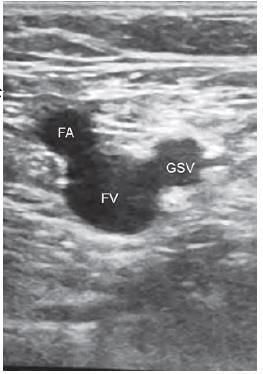

The sign seen on USG while locating the long saphenous vein and common femoral vein lying medial to the common femoral artery is called as: (NEET-PG 2020p)

The Mickey Mouse sign is believed to illustrate the typical anatomy of the femoral artery, femoral vein, and greater saphenous vein when viewed via ultrasound just below the inguinal crease. The ultrasound image at the area indicated by the arrow (femoral triangle) displays the lumen of the femoral artery (FA), femoral vein (FV), and great saphenous vein (GSV) as they enter the femoral vein.